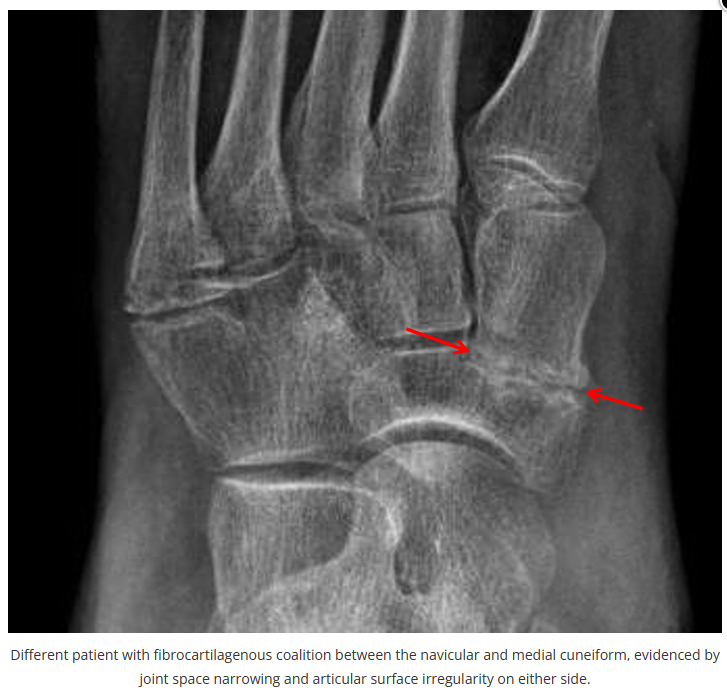

今天是腕部与手的X线片。所有X线片都

带有标注和说明

,可以选择长按图片,

自动翻译相关说明